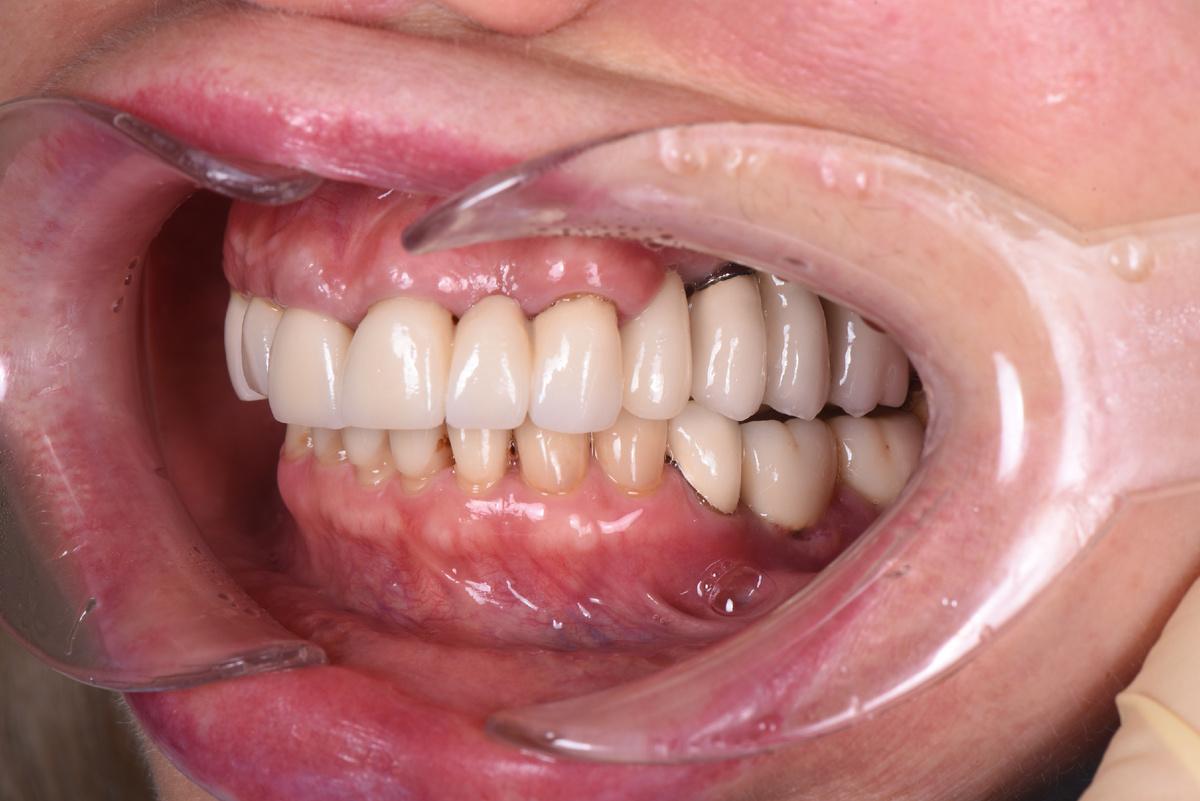

Первая примерка :

Верхняя челюсть: 2 мостовидных протеза в жевательных отделах с опорой на 3 имплантата и мост на 6 единиц с опорой на 4 собственных зуба

Следующий шаг — коронки на нижние зубы:

Завершающий этап — после протезирования на имплантатах на нижней челюсти слева, в той области, где костная ткань восстанавливалась дольше всего